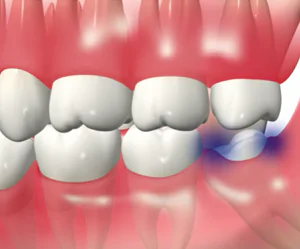

親知らずは横に傾いたり、埋まったまま出てこない場合が多く、手前の歯までむし歯になったり、歯ぐきが腫れたりしてトラブルの原因になってしまいます。親知らずはまっすぐ生えている場合には通常の抜歯で対応できますが、横向きに生えていたり、歯ぐきや骨に埋まっていたりする場合は、歯科口腔外科での処置が必要になります。当院ではCTを活用した精密な診断により、神経や血管の位置を把握したうえで、必要に応じて大学病院などの高度医療機関と連携しながら、安全性に配慮した抜歯を行います。

親知らずは、生え方によってさまざまなトラブルを引き起こします。横向きや斜めに生えてくると、痛みや腫れを感じることがあり、歯ぐきの一部に埋まったままの状態でも同じような症状が出ることがあります。

このような状態を放置すると、歯並びが乱れたり、隣の歯が虫歯や歯周病になるリスクが高まったりするため、症状がある場合は早めの抜歯をおすすめします。